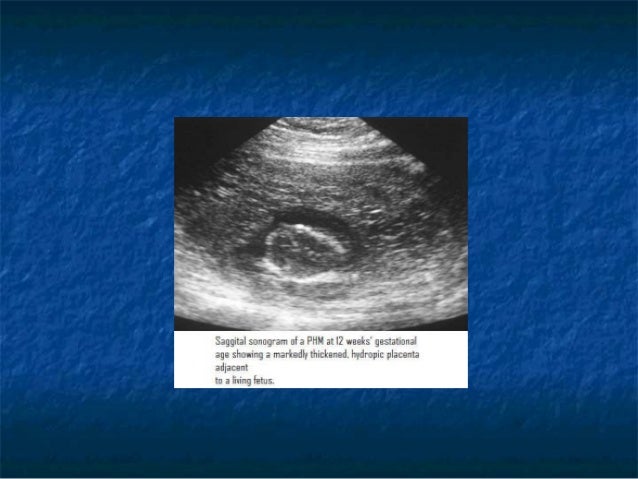

Molar pregnancy. An in-depth review of molar pregnancy: classification, pathogenesis. Molar pregnancy